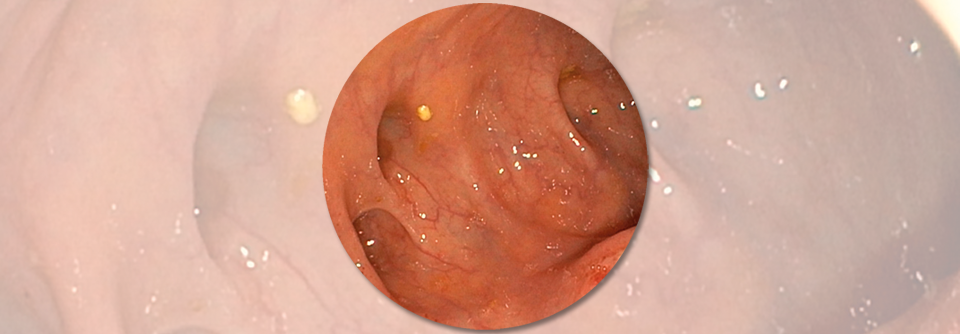

Als Divertikulitis wird eine Erkrankung des Dickdarmes bezeichnet, bei der sich die Divertikel (Ausstülpungen der Darmwand) entzünden. Die Divertikulose des Kolons, eine Vorstufe der Divertikulitis, ist eine der häufigsten gutartigen Veränderungen des Gastrointestinaltrakts. Allerdings handelt es sich um Pseudodivertikel, also Ausstülpungen der Mukosa und Submukosa an Eintrittsstellen der Arteriolen. Während die Divertikulose bei unter 40-Jährigen selten ist, steigt die Prävalenz mit zunehmendem Lebensalter auf ca. 65 % bei 85-jährigen an. Menschen, deren Darm Divertikel ausgebildet hat, erkranken zu etwa 12 - 25 % an einer Divertikulitis.

Die Diagnostik erfolgt mittels einer klinischen Untersuchung, Sonografie sowie Computertomografie des Abdomens. Manchmal wird auch auf eine Koloskopie zurückgegriffen, die jedoch gerade in einer akuten Phase ein erhöhtes Perforationsrisiko birgt.